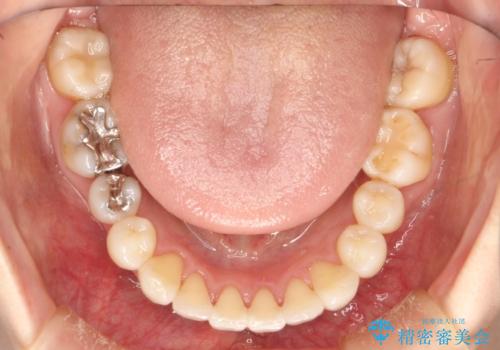

裏側のワイヤー矯正 抜歯して前歯をしっかり後ろに下げる

- 出っ歯が気になるとのことで来院されました。

上顎の、前から4番目の歯を左右1本ずつ抜歯して前歯を後方に下げる計画としました。

目立たずに矯正をご希望でしたので、裏側矯正で治療を行いました。

上下裏側矯正であったため、舌に傷や口内炎ができるなどつらい経験もされましたが、目立たずに治療できたことに喜んでいただけました。